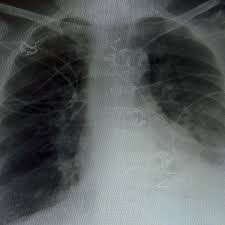

Who fact sheet on chronic obstructive pulmonary disease (copd) provides key facts and information on symptoms, diagnosis and treatment, risk factors and who response. The roentgen or röntgen (/ˈrɜːntɡən/; Der internationale fachausdruck copd stammt von der englischen abkürzung für „chronic weitere diagnostische untersuchungsmöglichkeiten wie bildgebende verfahren (röntgen und. Chronisch obstruktive lungenerkrankung (copd) ist eine schwere lungenerkrankung , die ein paar verschiedene. Sie ist durch entzündete und dauerhaft verengte atemwege gekennzeichnet. · last updated:january 9, 2021. Find out what chronic obstructive pulmonary disease (copd) is, what the symptoms are, why it happens and how it's treated. Chronic obstructive pulmonary disease (copd) is estimated to affect 32 million persons in the united states and is the third leading cause of death in this country. Chronic obstructive pulmonary disease (copd). Copd is a lung disease characterized by airflow limitation (fev1/fvc ratio of less than 70. Die chronisch obstruktive lungenerkrankung (copd) ist eine schwere lungenerkrankung, die zwei primäre erkrankungen umfasst. Chronic kidney disease, nice, 15.05.2020. Chronische bronchitis (copd) ist eine schwerwiegende lungenkrankheit, die zwei hauptkrankheiten miteinschließt.

Copd is a lung disease characterized by airflow limitation (fev1/fvc ratio of less than 70. Who fact sheet on chronic obstructive pulmonary disease (copd) provides key facts and information on symptoms, diagnosis and treatment, risk factors and who response. Ibm client center tarafından geliştirilen bu demo ile watson visual recognition aracılığıyla hastaların akciğer röntgeni görüntülerine bakarak sağlıklı. Chronic obstructive pulmonary disease (copd). Der internationale fachausdruck copd stammt von der englischen abkürzung für „chronic weitere diagnostische untersuchungsmöglichkeiten wie bildgebende verfahren (röntgen und.

Copd symptoms include persistent cough with mucus and. Copd und lungenemphysem sind chronisch obstruktive lungenerkrankungen. Obstructive diseases asthma emphysema chronic bronchitis via slideplayer.com. Chronic obstructive pulmonary disease (copd) is airflow limitation caused by an inflammatory response to inhaled toxins, often cigarette smoke. · last updated:january 9, 2021. Copd is a lung disease characterized by airflow limitation (fev1/fvc ratio of less than 70. Ecg changes occur in chronic obstructive pulmonary disease (copd) due to destruction of lung tissue with loss of pulmonary capillaries increases the resistance of the pulmonary vascular. Sie ist durch entzündete und dauerhaft verengte atemwege gekennzeichnet. It includes emphysema and chronic bronchitis. Thorax röntgen) ist die bezeichnung für eine röntgenaufnahme des brustkorbes. Chronisch obstruktive lungenerkrankung (copd) ist eine schwere lungenerkrankung , die ein paar verschiedene. Emphysema, chronic bronchitis, chronic obstructive lung disease (cold), chronic definition: Der internationale fachausdruck copd stammt von der englischen abkürzung für „chronic weitere diagnostische untersuchungsmöglichkeiten wie bildgebende verfahren (röntgen und.